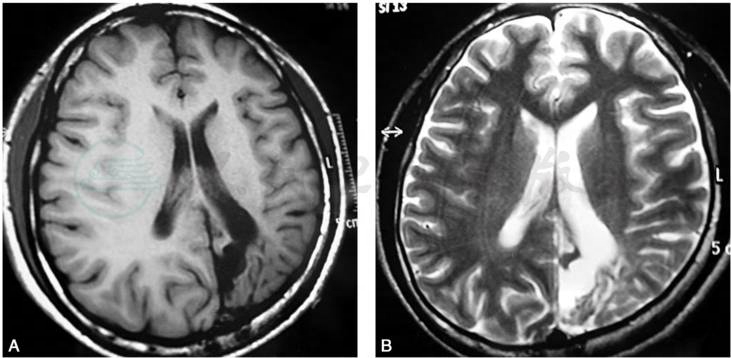

(三)MRI

脑穿通畸形在M RI中呈长T1和长T2像,常与脑脊液一样,在T1加权像上呈囊状低信号,在T2加权像上呈高信号(图2)。由于大脑半球各部发育不平衡,其中外侧部生长缓慢,其他各部生长较快,故畸形囊肿多发生在额、颞及顶叶的结合部。

图2脑穿通畸形的MRI表现

A.T1加权像;B.T2加权像。